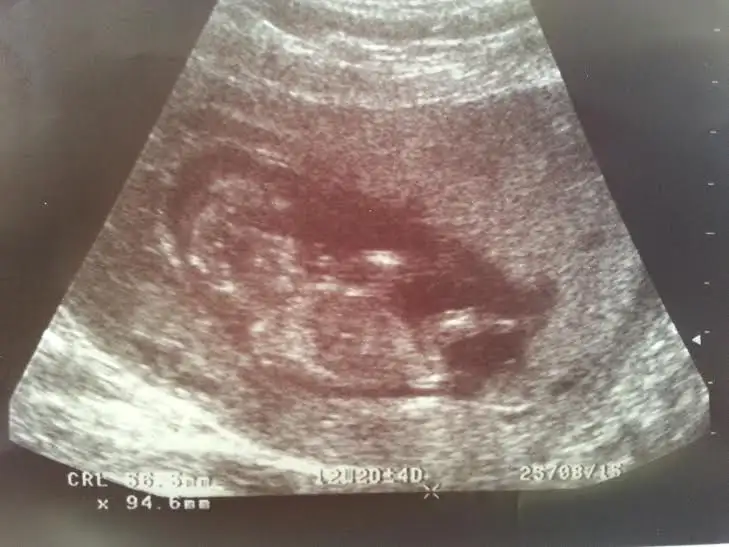

Daha küçük olduğu icin anlayamadim sanirim az daha sabretbaşı sol tarafa 10.hafta

Kızlar sizce cinsiyeti ne bilenler söyleyebilir mi

BENCE ERKEK :)Kızlar sizce cinsiyeti ne bilenler söyleyebilir mi

o gördüğümüz nub ise açılı sanırım erkekKizlar bnm bebisimede bakarmisinz rica etsem,doktor 16.haftayibekle dedi,biz 13. Haftadayiz..

Canım ilk fotografa bakmamıştım bebek tam yan değil hafif arkası dönük sidellanın tahmini doğru sanırım...Cnm bidaha baksana ya,sidella2011 nub yan yatmis kiz dedi..